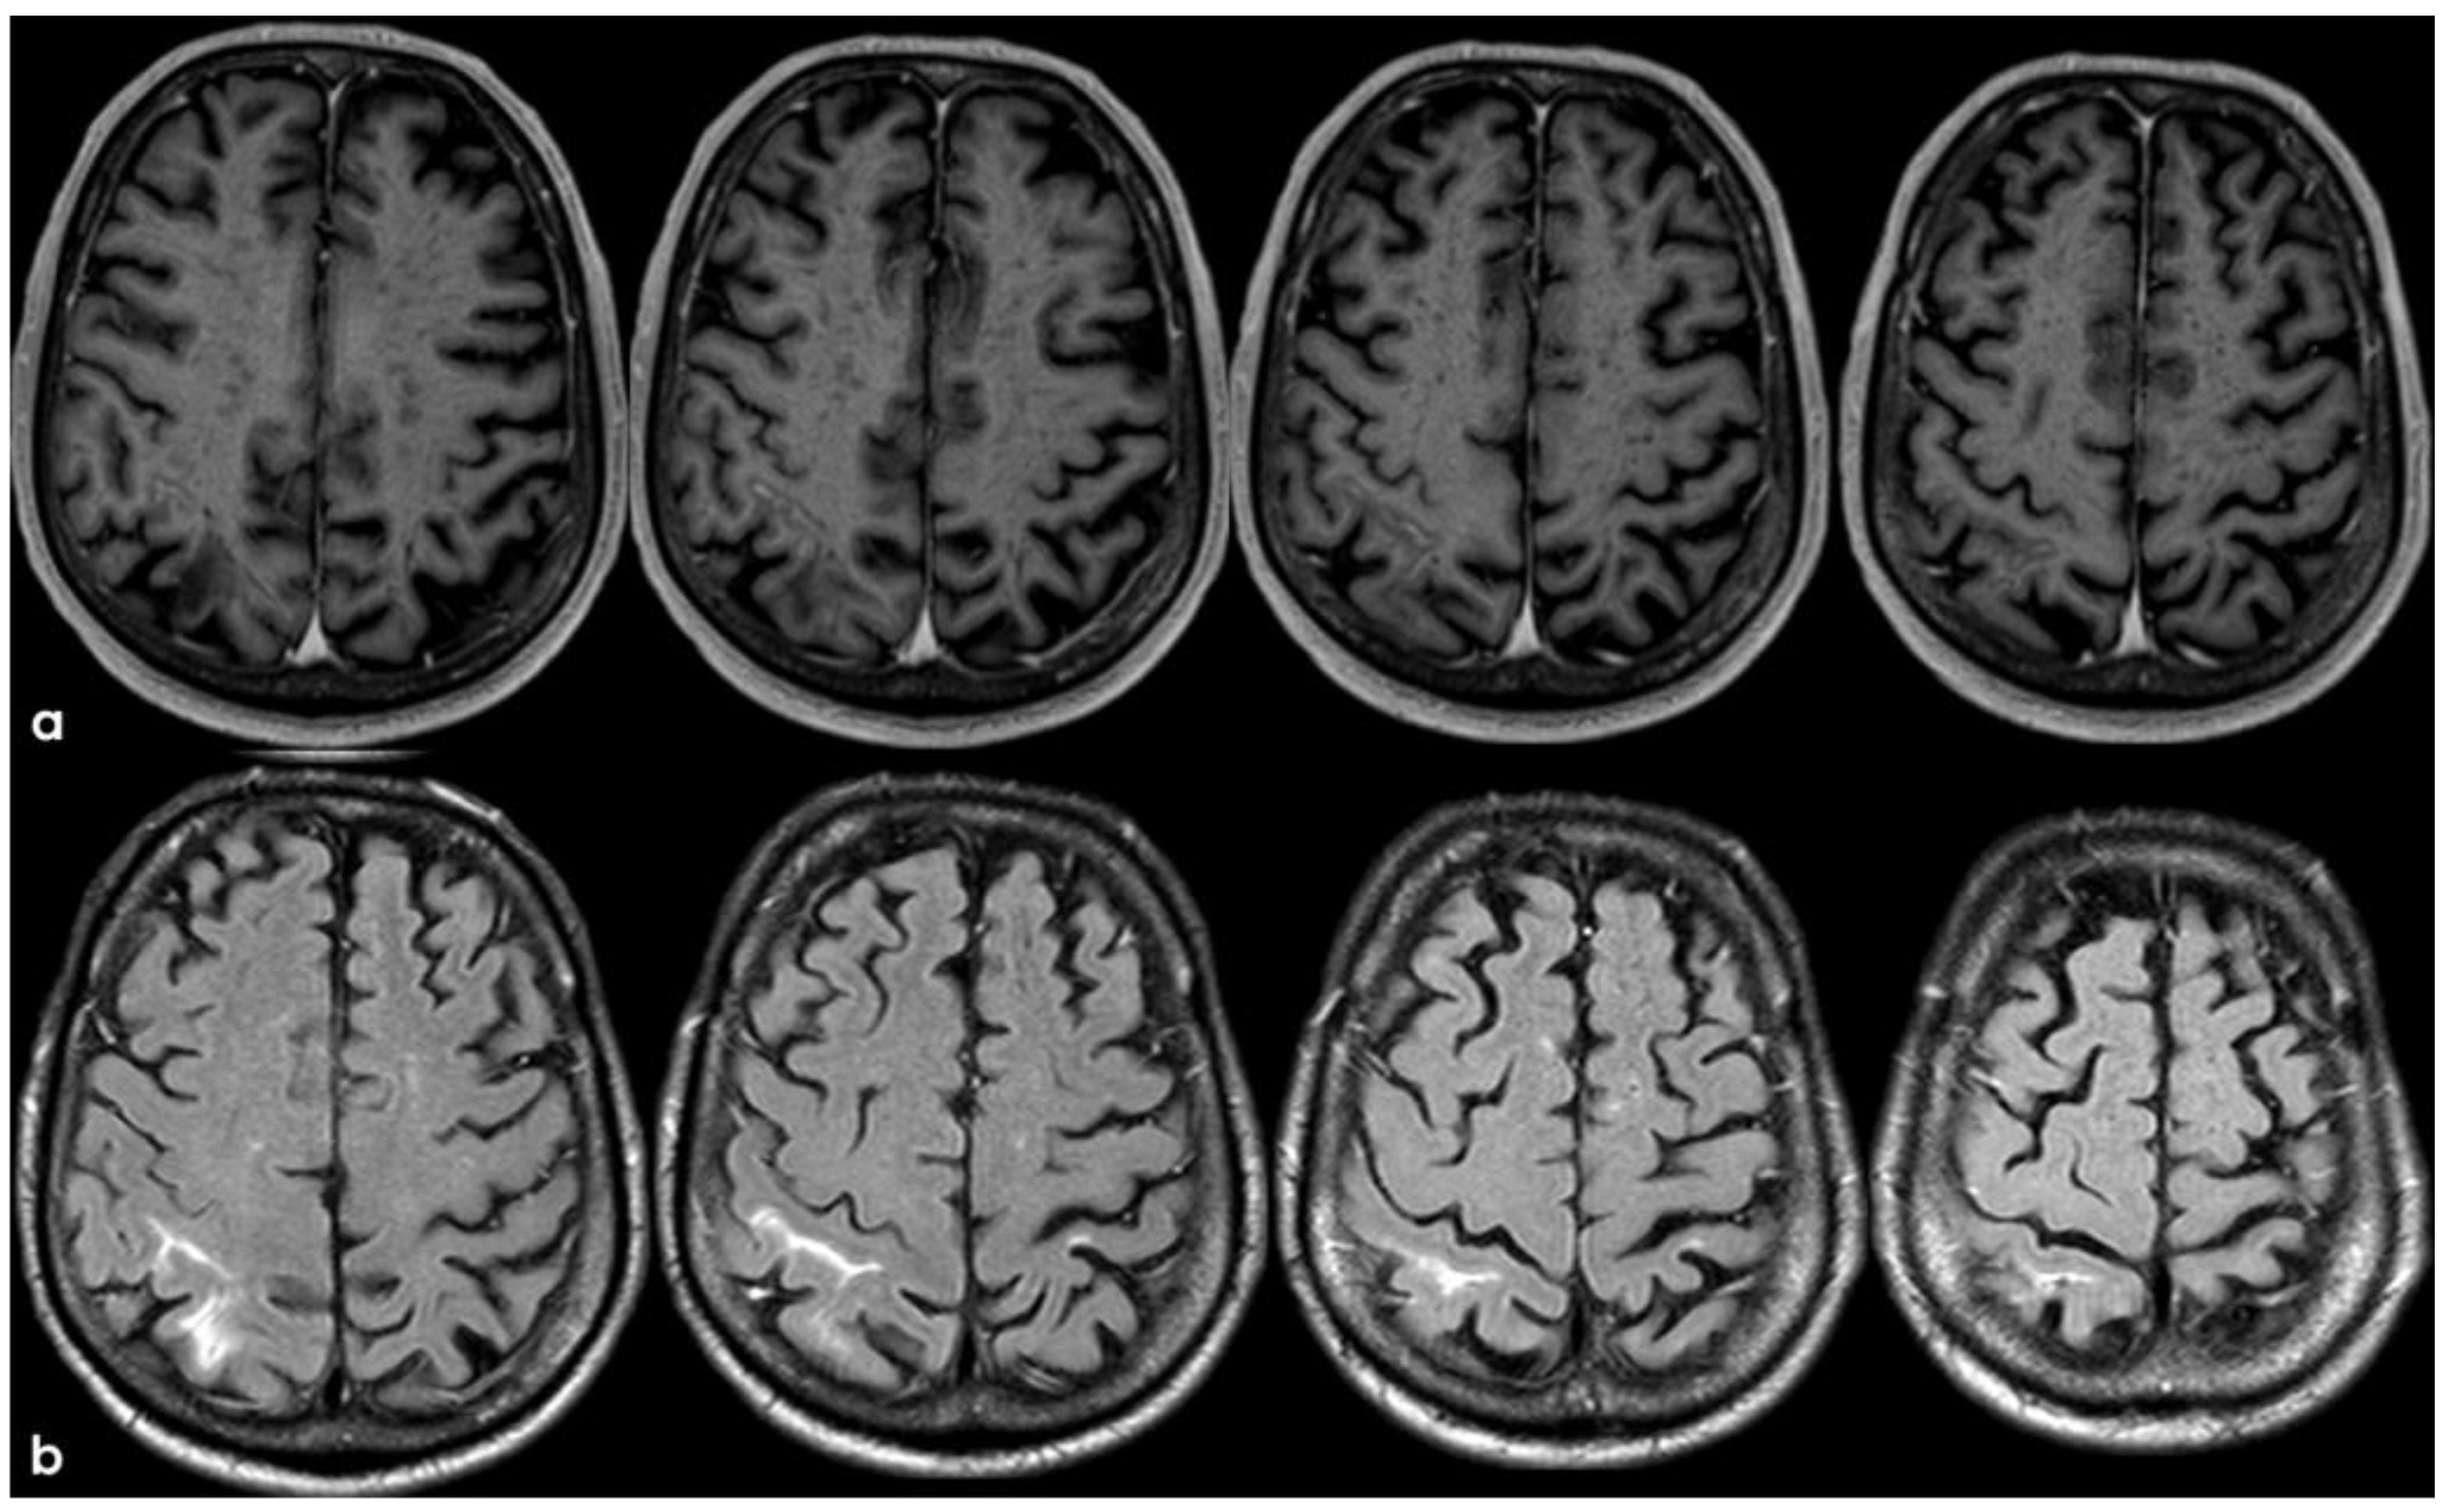

3. May 2014: CAA-Related Inflammation

5. February 2017: First Recurrent CAA-Related Inflammation

7. April 2018: Second Recurrent CAA-Related Inflammation

8. April 2018: Third Recurrent CAA-Related Inflammation